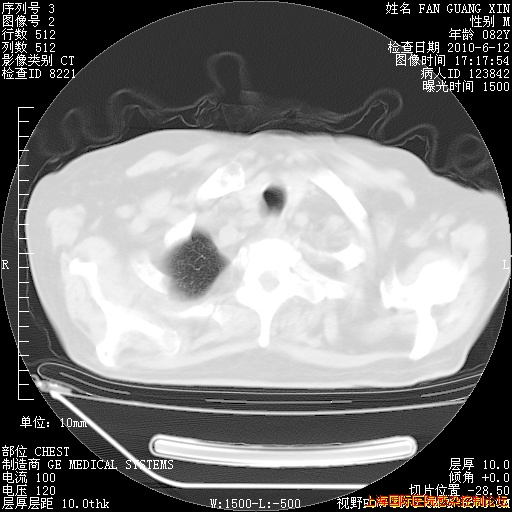

今天复查CT

今天CT

整整相隔30天的肺部CT好像有所好转啊。甲强龙减量第3天,需要观察体温。

海管,自昨日你和我通完话后,不知您岳父消化道症状有无缓解?体温怎样?阅读7.12日胸部ct,个人认为目前激素治疗是有效的,甲强龙减量是适宜的。因在抗痨治疗,需密切观察肝功、肾功能和血常规。不过,老年、长期住院和大量使用激素,很担心菌群失调发生